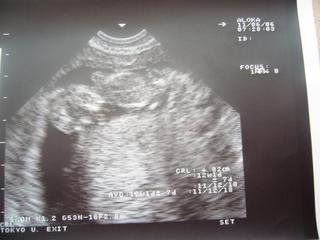

Inak, bola som v pondelok na poradni a USG, len som sa sem nejako nedostala. Pridávam fotky z USG. Zatiaľ mám - 2 kg. V pondelok som bola podľa menzesu 11+6 tt. Podľa USG má jedno 48,2 mm - to vychádza na 12+1 tt v pondelok a druhé 48,5 mm - a to bolo veľké na 12+2 tt., takže pekne rastieme. Na jednej je jedno, na druhej sú obe a na tretej je druhé. Jedno je dole hlavičkou a druhé bolo priečne.